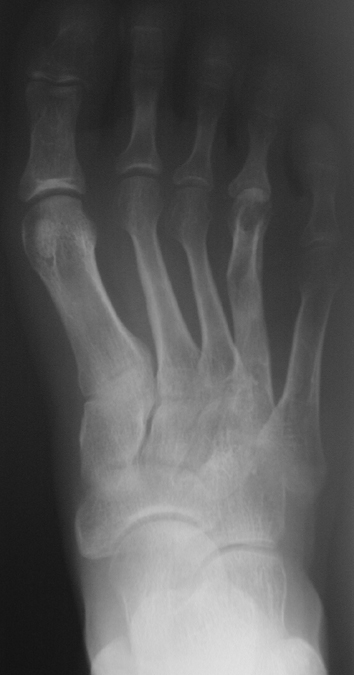

El parmağı (metakarp) ve ayak parmağı (metatars) kısalıkları doğuştan tek başına, geniş bir sendrom grubuyla birlikte, travma sonrası, Freiberg hastalığı (avasküler nekroz) sonrası görülebilir.

Doğuştan metakarp ve metatars kısalığının görülme sıklığı 1/1000’den azdır. Kadınlarda erkeklere göre 5 kat daha fazla görülür ve sıklıkla (%72) iki taraflıdır. En sık 4. parmak tutulur. Bu tür olgularda sorunun nedeni tam olarak bilinmemekle brlikte deformitenin genellikle epifiz plağının erken kapanmasından kaynaklandığı düşünülmektedir.

Metakarp kısalığında kozmetik görünümün bozulması ve dominant elin kullanımı sırasında yorulma, metatars kısalığında ise kozmetik haricinde metatarsalji, kısa parmağın dorsale kayması sonucu deformite oluşması, plantar yönde açılanması sonucu ağrı ve bası ülserleri, ve ayakkabı giymede zorluk nedeniyle ameliyat gerekebilir.

Doğuştan metakarp ve metatars kısalıklarının redavisi için pek çok teknik tanımlanmakla birlikte en çok akut uzatma sonrası kemik uçlarına greft konması ve distraksiyon osteogenezi (kallotasis) kullanılmaktadır. 1 cm.den daha fazla uzatma gereken olgularda kallotasis yöntemi önerilmektedir. Kliniğimizde de metatars ve metakarp uzatma için unilateral eksternal fiksatör ve sirküler eksternal fiksatör yardımıyla distraksiyon osteogenezi yöntemi tercih edilmektedir.